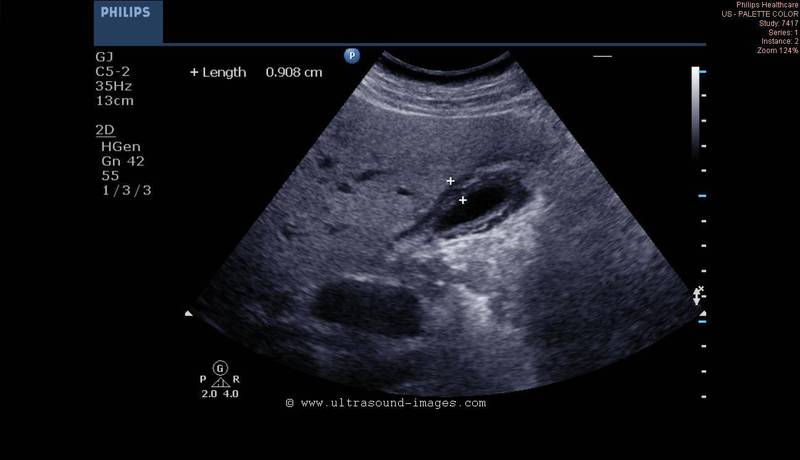

Tiny polyp of the gall bladder wall

Small gall bladder polyp. This ultrasound image shows a small polyp of the inferior wall of the gall bladder. Note the small base of the polyp, suggesting its benign nature. Such polyps are usually the result of chronic inflammation. Ultrasound image courtesy of Dr. Ravi Kadasne, UAE. He used a Philips IU22 machine to obtain this image.